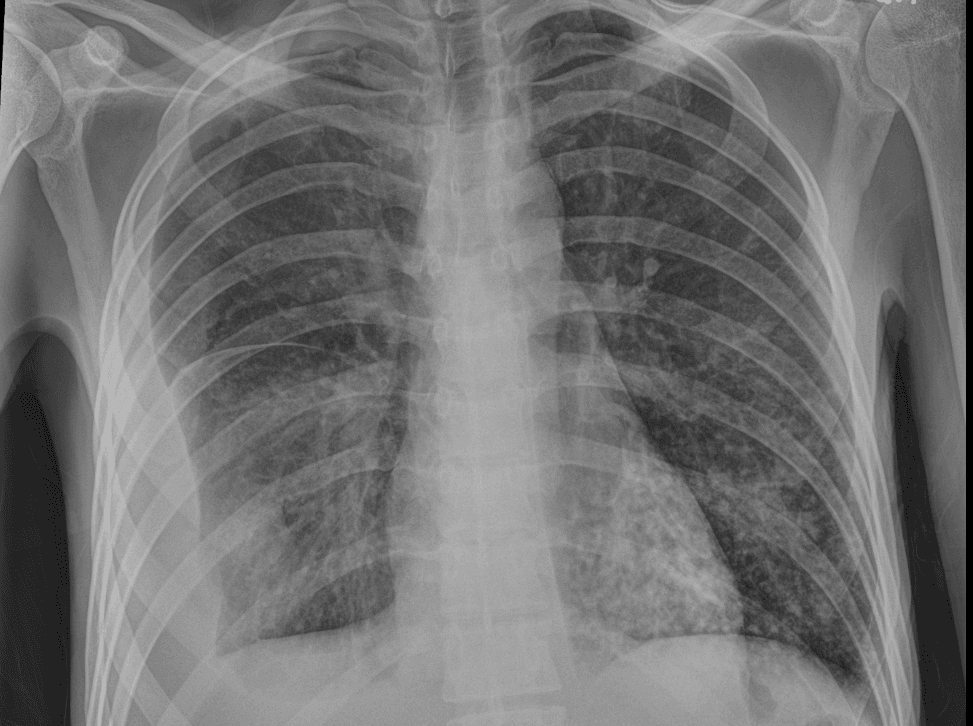

On examination, he is cachectic but not in acute distress. Temperature is 36.7 C, heart rate 103/min, blood pressure 91/63 mmHg, and respiratory rate 18/min. He has pale conjunctivae, decreased air entry on the right hemithorax, right lower-quadrant abdominal tenderness, and 2+ bilateral lower-extremity edema. A chest radiograph is obtained as part of the inpatient workup.

Chest X-ray